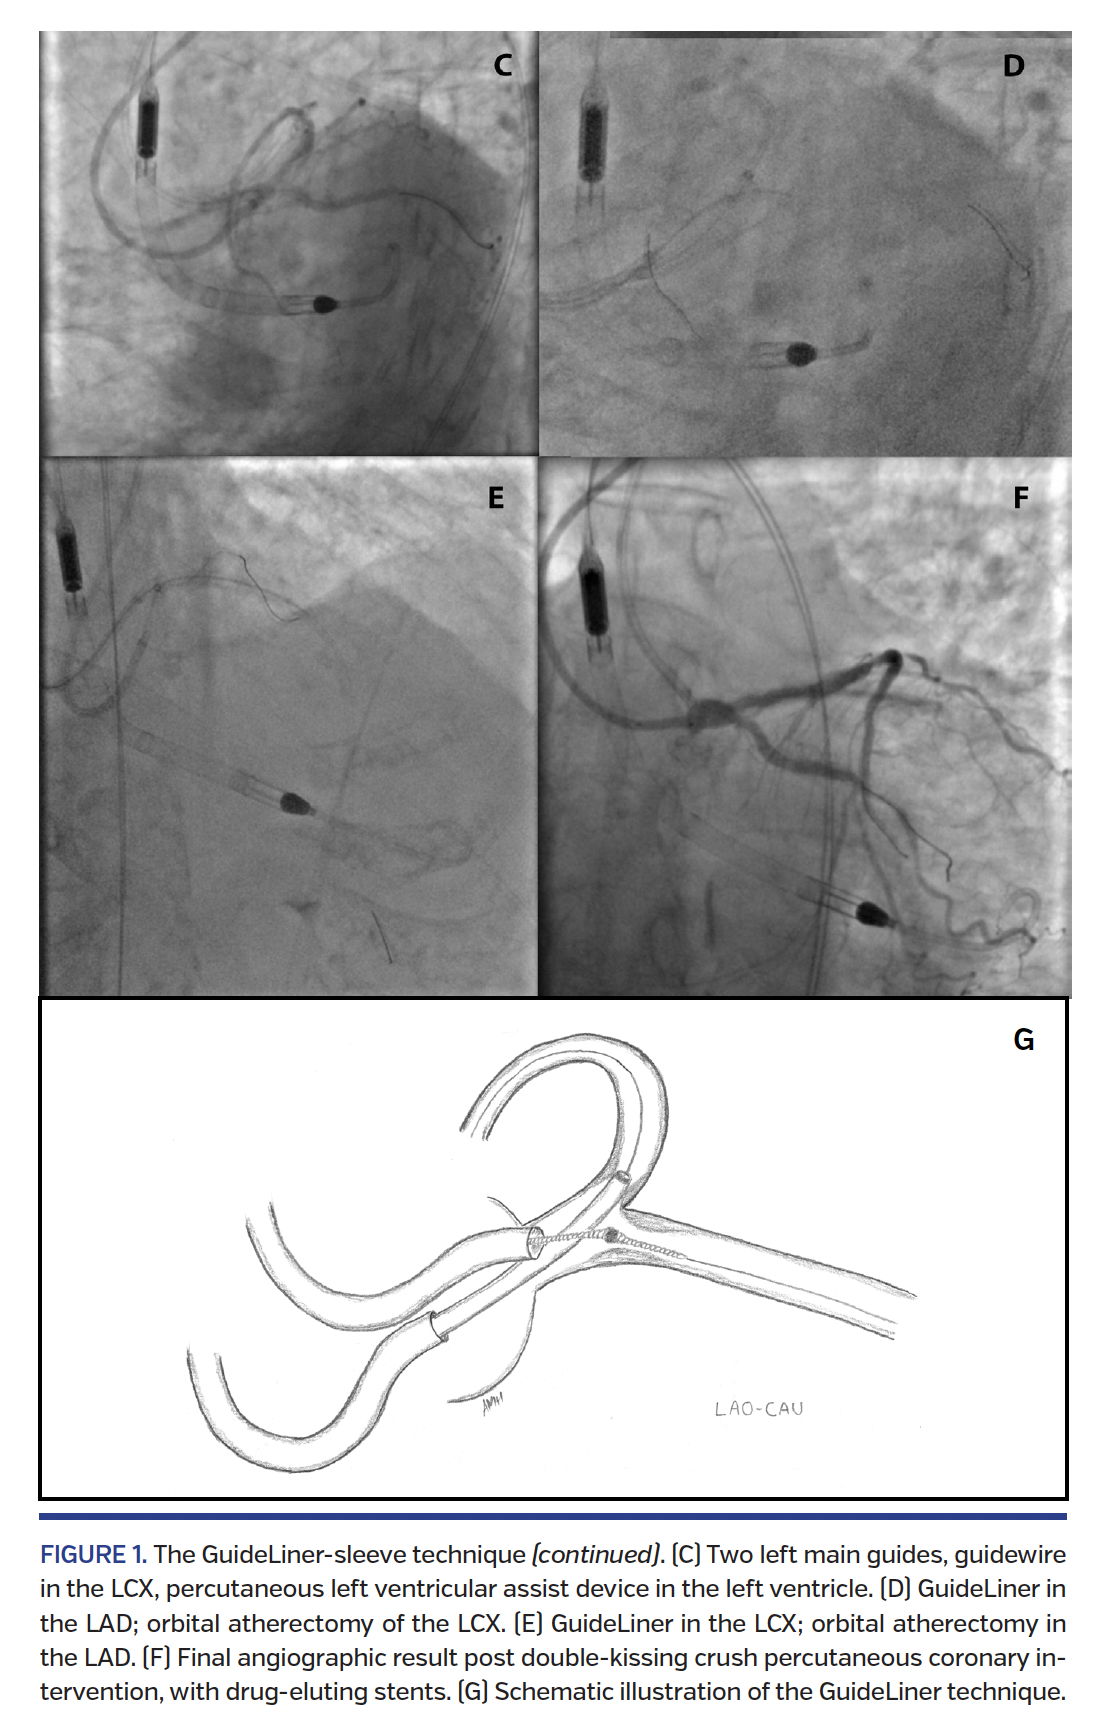

A percutaneous left ventricular assist device was inserted for hemodynamic support. We devised a novel “GuideLiner-sleeve” technique to perform orbital atherectomy of the ostial LAD and LCX (Figures 1B-1G), protecting each vessel with a coronary guidewire while performing atherectomy of the other vessel. We used two guiding catheters from bilateral radial arteries to wire both the LAD and LCX. We advanced a GuideLiner catheter (Vascular Solutions) as a sleeve over the guidewire in the LAD and performed orbital atherectomy of the LCX ostial lesion, then reversed the configuration to perform atherectomy of the LAD while protecting the LCX. Following orbital atherectomy, left main bifurcation stenting was successfully completed using the double-kissing crush technique.1 The patient was subsequently discharged home in stable condition and remains well at follow-up.

Our novel GuideLiner-sleeve technique enabled use of atherectomy in calcific ostial lesions of the LAD and LCX. Due to the differential sanding effect, the GuideLiner effectively protects the second guidewire, allowing safe access to the second major epicardial vessel throughout the procedure.